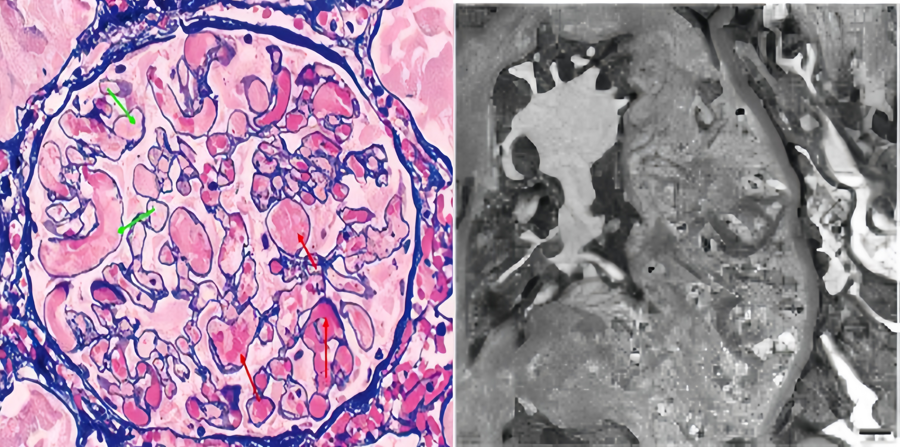

肾穿刺活检结果“一锤定音”,通过光学显微镜(光镜)和电子显微镜(电镜)再次明确诊断,均证实了肾内血栓性微血管疾病的特征性改变。李女士最终被明确诊断为非典型溶血性尿毒综合征。

TMA急性期典型的肾小球改变(左);肾脏TMA电镜表现(右)